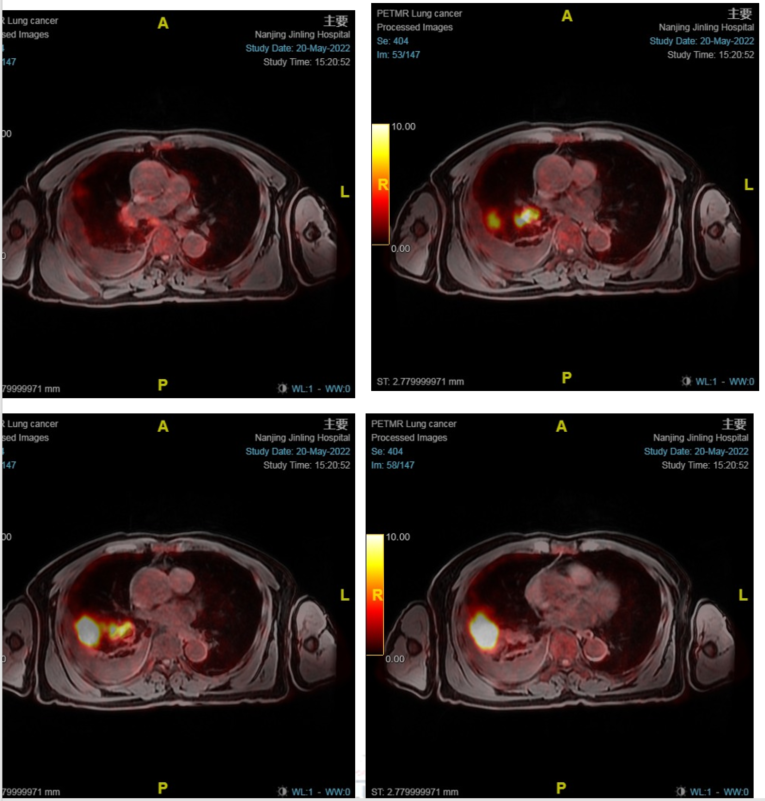

2022-05-20PET/MRI示:

1. 右肺下叶肿块(大小约62mm×41mm)及右肺门肿大淋巴结,代谢明显增高,结合病史考虑右肺下叶肺癌并右肺门淋巴结转移:右侧锁骨上区、两肺门及纵隔内淋巴结多发大小不等淋巴结,代谢轻度增高,转移不除外:

图1.PET/MRI